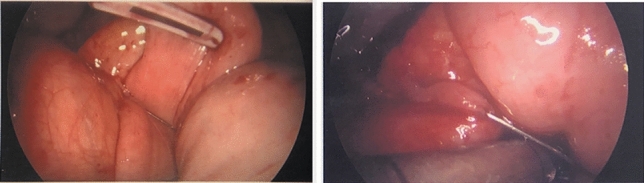

Methods and procedures: An 81-year-old Caucasian female was admitted to the emergency room with a complaint of 24-h epigastric pain, associated with nausea. She had history of a laparoscopic reduction of the foramen of Winslow internal hernia in our institution. CT scan of her abdomen showed a lesser sac internal hernia with an incarcerated colon and underwent a laparoscopic repair with a flap of falciform ligament and laparoscopic cecopexy. The surgery was successful.

Results: Foramen of Winslow hernias, a rare type of internal hernia. Internal hernias have an incidence rate of less than one percent, with Foramen of Winslow hernias accounting for only 8% of all internal hernias. The case at hand involves an 81-year-old Caucasian women who described a prior history of hypertension and a past laparoscopic reduction of the Foramen of Winslow internal hernia in the past. She had complaints of 24-h epigastric pain associated with nausea. She underwent a CT scan of her abdomen which revealed a lesser sac internal hernia with an incarcerated colon and was taken to the operating room where her Foramen of Winslow internal hernia was repaired laparoscopically using a flap of falciform ligament. The hernia contents included the ascending colon and ileum and were viable. A laparoscopic cecopexy and a flap of falciform ligament were done. The surgery was successful.

Conclusion: Foramen of Winslow internal hernias are exceedingly rare, as they account for approximately 8% of all internal hernias, which themselves have a precedence of less than 1%. Despite limited occurrence of Foramen of Winslow hernias, these hernias have mortality rates as high as 49%. Once diagnosed, several methods for repairing Foramen of Winslow hernias have been described. As surgical equipment and technology continue to improve, many surgeons have been switching from laparotomies to a laparoscopic approach. When the cecum shows signs of excessive movement, a cecopexy is often performed laparoscopically to limit such movement. In addition to cecopexy, a flap of falciform ligament was created in order to obliterate the space into the Foramen of Winslow. This novel approach has not been described in the literature. We strongly believe that it should be included as an option to treat these difficult hernias in the future.